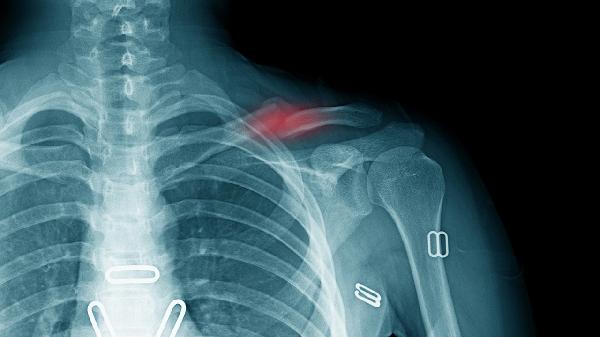

鎖骨骨折吃啥能恢復(fù)的快些

鎖骨骨折后可通過高蛋白飲食、鈣質(zhì)補(bǔ)充、維生素D攝入、抗氧化食物及適量膠原蛋白促進(jìn)恢復(fù)?;謴?fù)速度主要與營養(yǎng)攝入、骨折類型、年齡、康復(fù)訓(xùn)練及并發(fā)癥控制等因素相關(guān)。

鎖骨骨折恢復(fù)期需建立科學(xué)的飲食計(jì)劃,每日保證3-4餐均衡營養(yǎng)。急性期過后可逐步增加低強(qiáng)度上肢活動,如握力訓(xùn)練、鐘擺運(yùn)動等促進(jìn)血液循環(huán)。避免吸煙飲酒影響骨愈合,控制咖啡因攝入減少鈣流失。睡眠時保持30-45度半臥位減輕疼痛,定期復(fù)查X線觀察骨痂形成情況。若出現(xiàn)異常腫脹、持續(xù)疼痛或皮膚感覺異常需及時就醫(yī)。